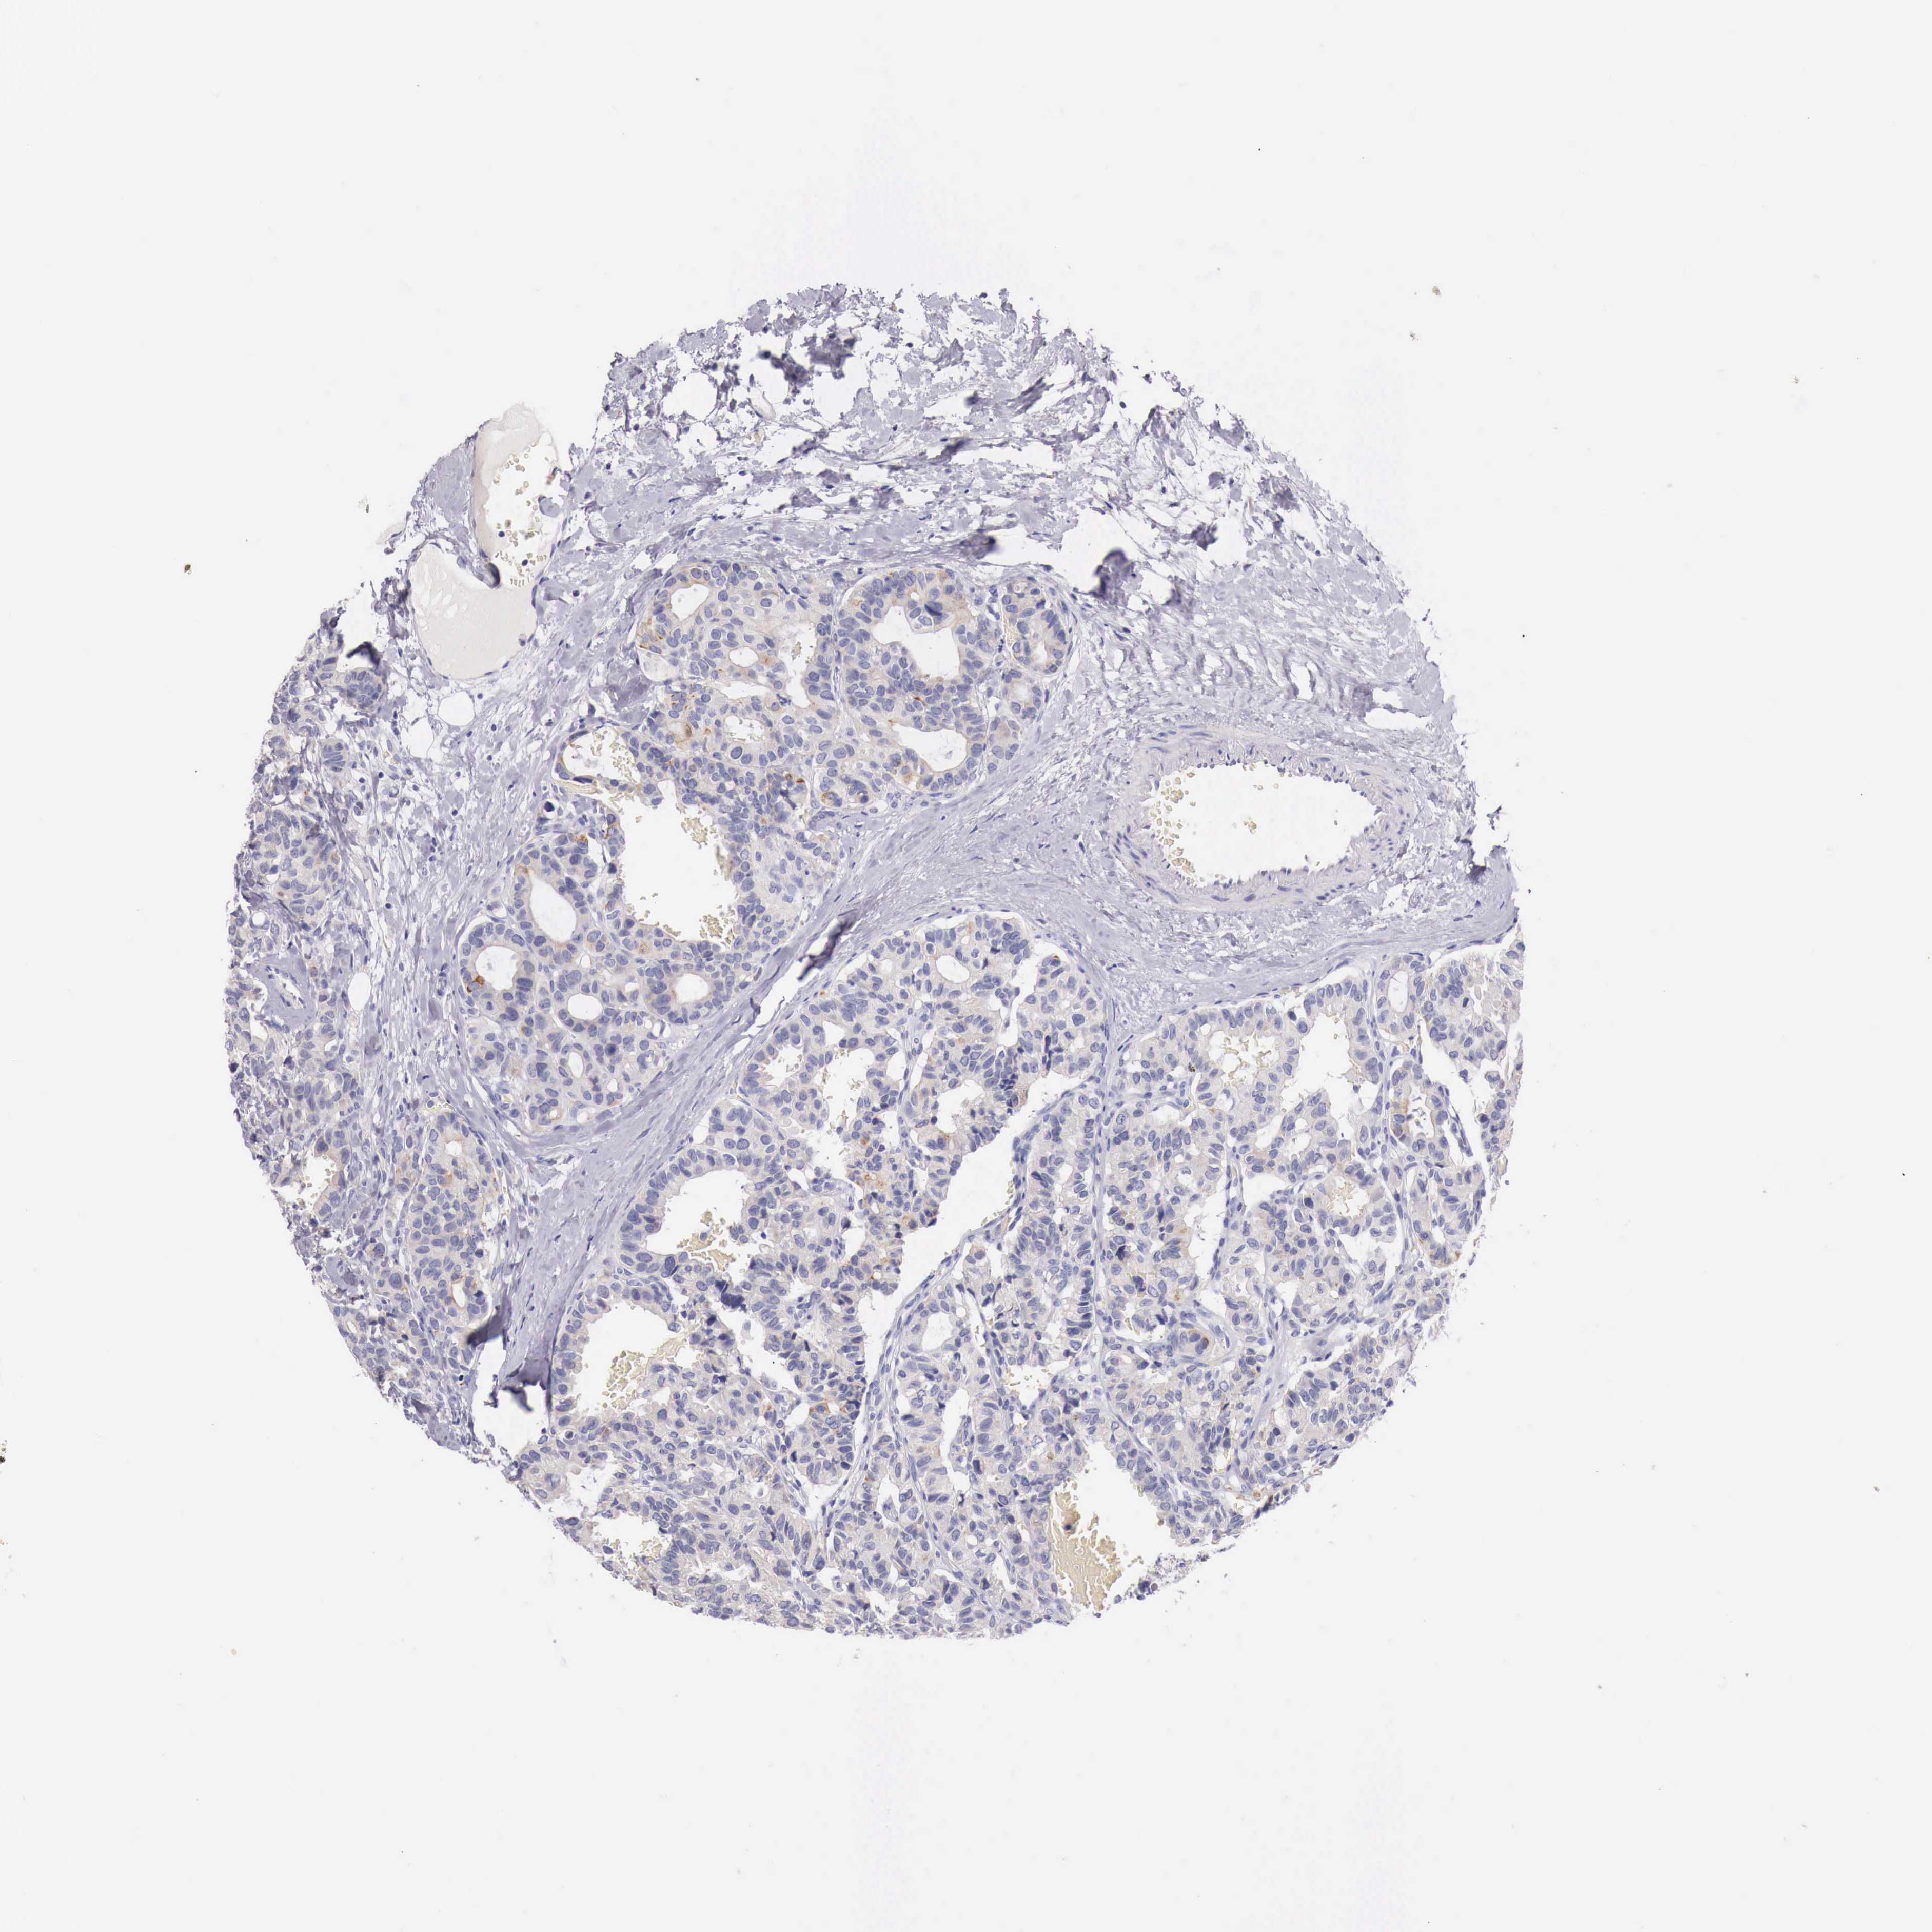

CANCER BREAST CANCER Show tissue menu

BRCA TCGA BRCA VALIDATION PROTEIN EXPRESSION